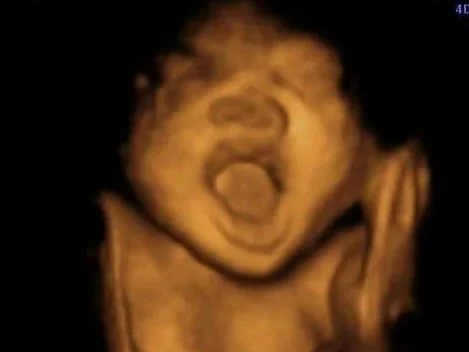

3D / 4D Well-Being Scan

(From 22-35 weeks gestation)

Our 3D / 4D Well-Being Scan is a special experience designed to help you connect with your baby later in pregnancy, following your 20-week NHS scan and prior to birth.

• 3D and 4D ultrasound scan